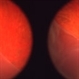

- pre-retinal membrane, color photo, ultrasound, stereo pair

- Ultrasound and color photo stereo-pair with next slide demonstrating sever pre-retinal fibrous membrane with contraction, possibly from PDR.